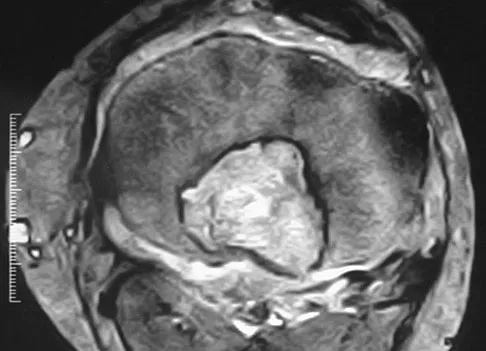

Question 61

A 16-year-old football player sustains a direct blow to the anterior aspect of his flexed right knee. Examination reveals a contusion over the anterior tibial tubercle and a small effusion. MRI scans are shown in Figures 33a through 33c. What is the most likely diagnosis?

Explanation

The MRI scans show disruption of the fibers of the PCL. Patients sustaining an isolated acute PCL injury can present with only minimal discomfort and have full range of motion. When examination reveals a contusion over the tibial tubercle and discomfort with the posterior drawer examination, with or without instability, a possible injury to the PCL should be considered. In acute injuries, the reported accuracy of MRI imaging for diagnosing PCL tears ranges from 96% to 100%. Resnick D, Kang HS: Internal Derangement of Joints: Emphasis on MRI Imaging. Philadelphia, PA, WB Saunders, 1997, pp 699-700. Harner CD, Hoher J: Evaluation and treatment of posterior cruciate ligament injuries. Am J Sports Med 1998;26:471-482.